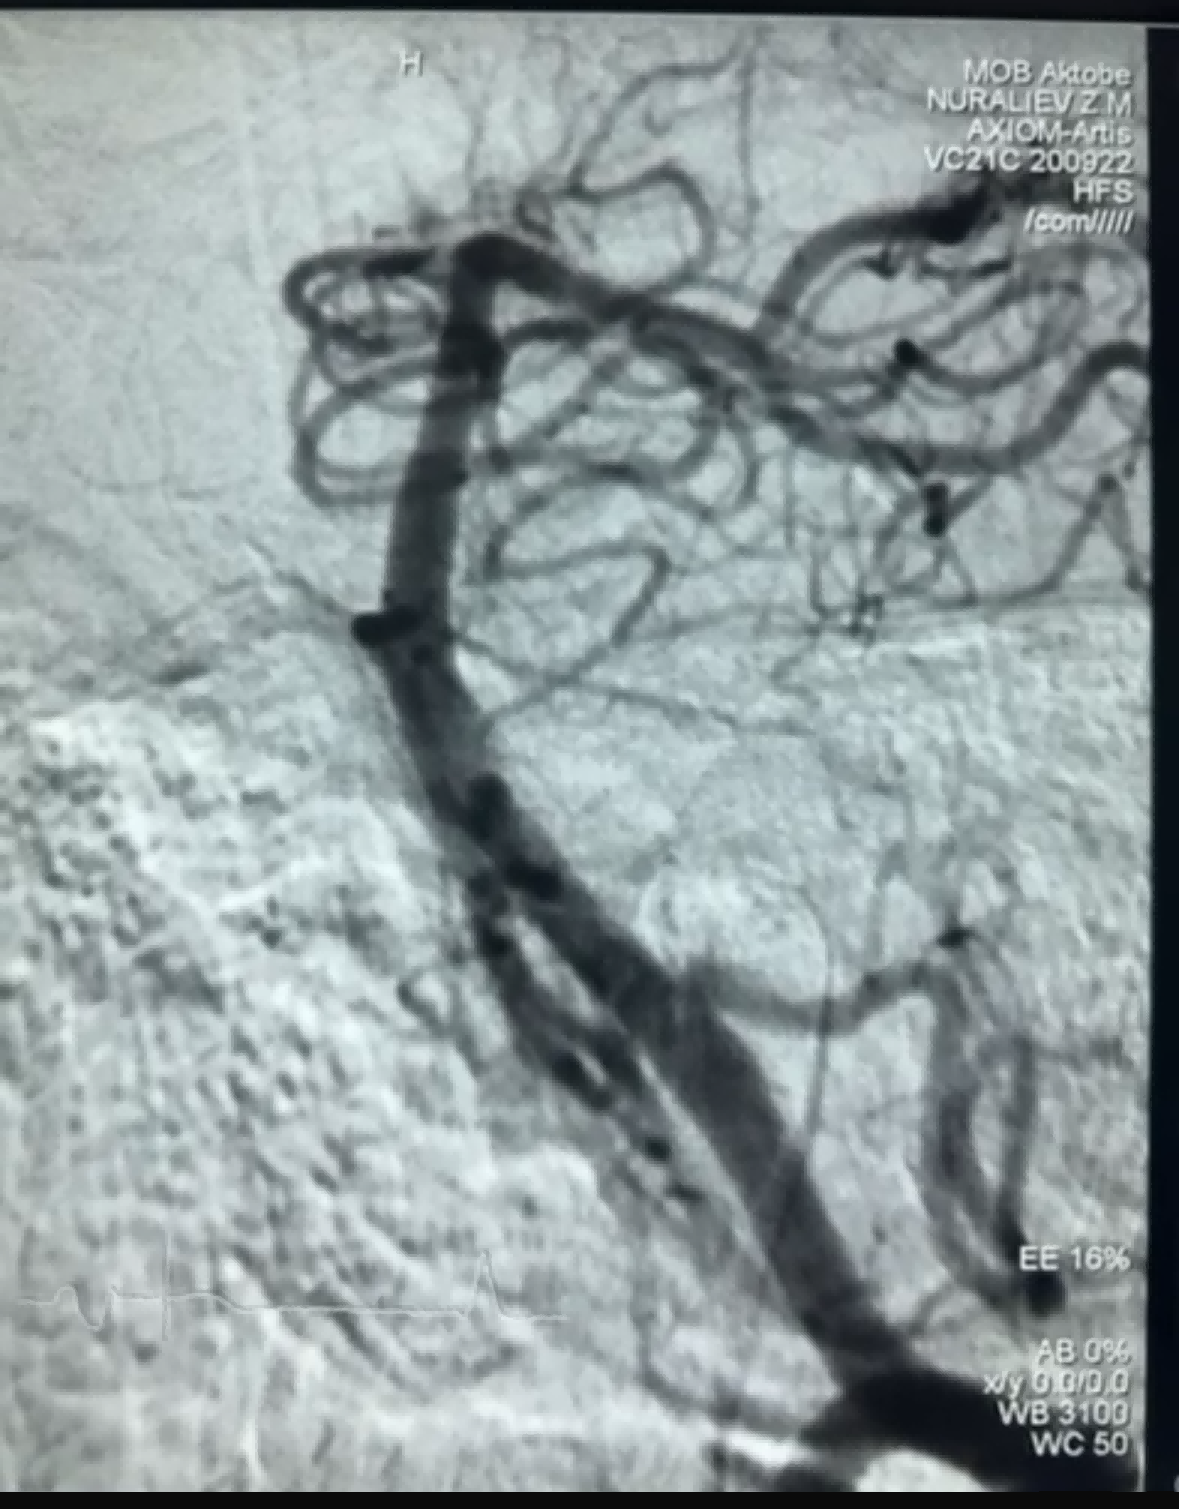

ล่าสุดมีเคสการทำ thrombectomy โดยใช้ Dredger Stent Retriever ของบริษัท NeuroSafe Medical Co., Ltd. สำเร็จ โดย Dredger Stent Retriever มีปลายอ่อนที่ไม่รุกราน ซึ่งช่วยลดความเสี่ยงต่อความเสียหายของเนื้อเยื่อชั้นในได้อย่างมาก และยังมีการออกแบบรูที่มีรูปร่างพิเศษเฉพาะตัว ซึ่งทำหน้าที่จับลิ่มเลือดโดยการหนีบการเปลี่ยนแปลงช่องว่างเป็นหลัก